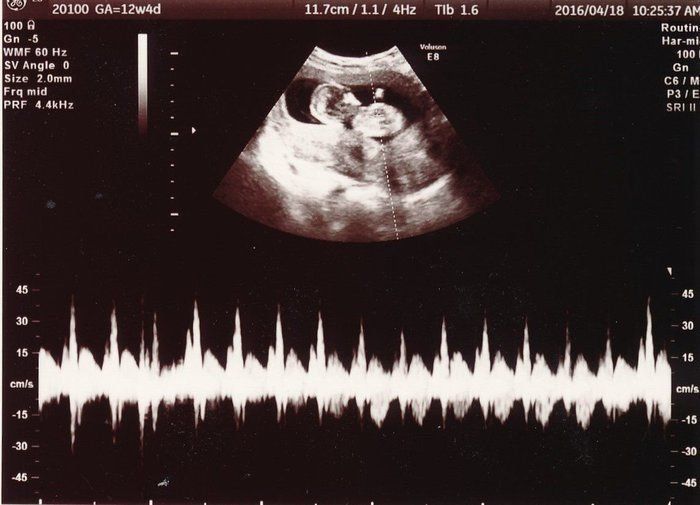

「背骨!足骨!ホントに人間がいる!」エコー画像を見る度、ゆっくり親になっていく私たち -